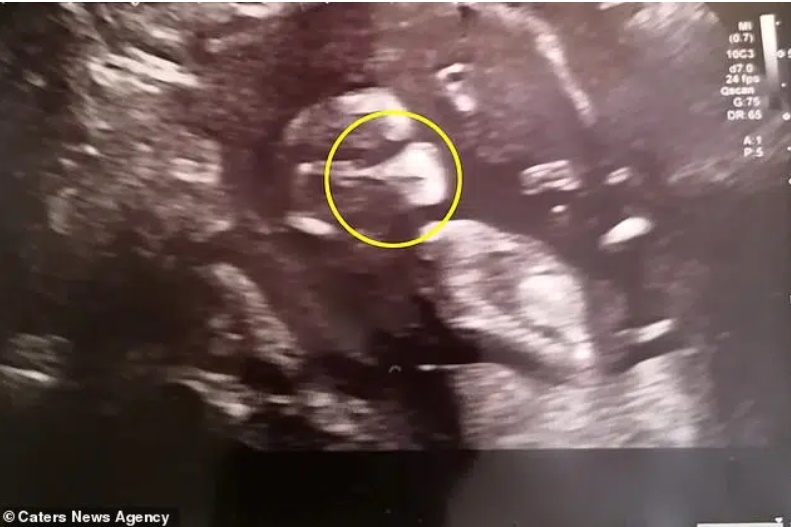

Samantha Spicer - 34 tuổi, đến từ Rushden, Northamptonshire, Anh cho biết cô đã rất hồi hộp và lo lắng khi đi siêu âm thai ở tuần 12. Song, trái ngược với tâm trạng của Samantha, hình ảnh siêu âm thai nhi đã khiến cô vô cùng ngạc nhiên và không ngừng cười khi con gái nhỏ của cô ấy trông như đang đeo khẩu trang trong bụng mẹ.

Hình ảnh siêu âm thai nhi con gái của Samantha Spicer (34 tuổi, đến từ Rushden, Northamptonshire, Anh).

"Những khoảng sáng trên màn hình siêu âm đã tạo ra hình ảnh giống như một chiếc khẩu trang trên khuôn mặt của con gái tôi. Ngay khi siêu âm, các bác sĩ ở đây và tôi đã cười lớn. Hình ảnh đó thật sự rõ ràng.

Chúng tôi còn thầm đoán rằng, liệu có phải con tôi đã biết trước rằng mẹ của nó bị nhiễm COVID-19 nên đã chuẩn bị sẵn sàng để đối phó với dịch bệnh từ trong bụng mẹ hay không.", Samantha nhớ lại.

Trong một hình ảnh khác được thể hiện trên màn hình siêu âm, các bác sĩ và Samantha còn nhìn thấy được cô bé như đang giơ tay để vẫy chào mọi người.